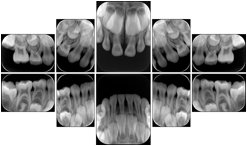

2. A patient requests cosmetic surgery to enhance their facial appearance. The case requires consultation between an orthodontist in New York and an oral surgeon in California. The cephalometric series of 2D projections constructed from the volumetric CT data that is used for the discussion is arranged by a Structured Display for transfer between the two practitioners.

Cephalometric Series Structured Display

Figure OO-2. Cephalometric Series Structured Display